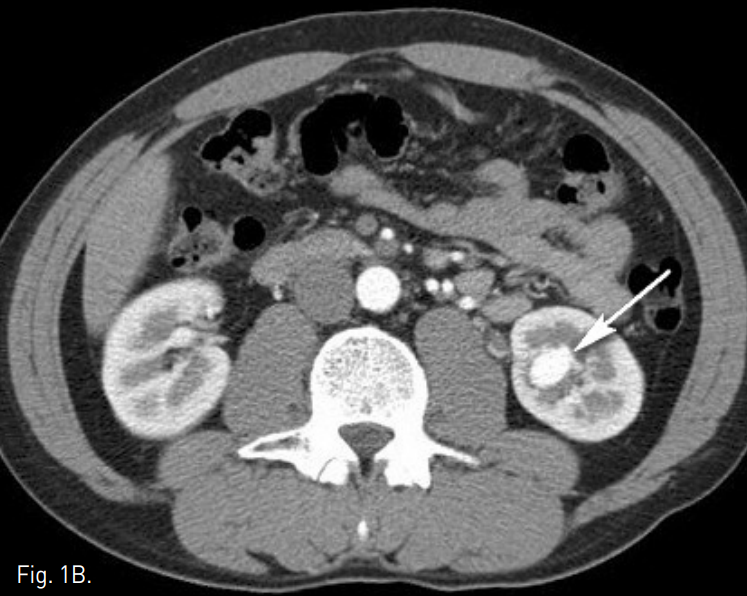

초음파에서 왼쪽 신장 하부에 1.3cm 크기의 낭성병변이 있으며, 내부에 mixed doppler signal이 관찰됨(Fig. 1A). 복부 CT에서도 동일한 위치에 혈관과 동일한 조영증강 양상을 보이는 1.7×1.3cm 크기의 혈관성 종괴가 있음(Fig. 1B).

Fig. 1

Renal doppler US and abdominal CT show a vascular mass suggesting nidus of AVM in lower pole of left kidney(arrow)